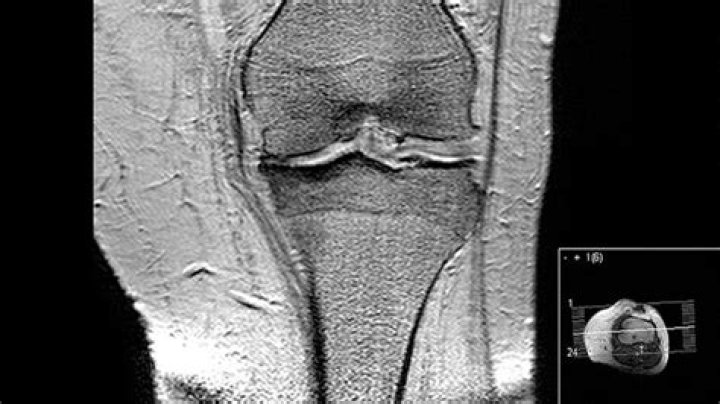

MRI is the most effective way to diagnose problems within any joint and the image sensitivity makes it the most accurate imaging tool available in detecti...